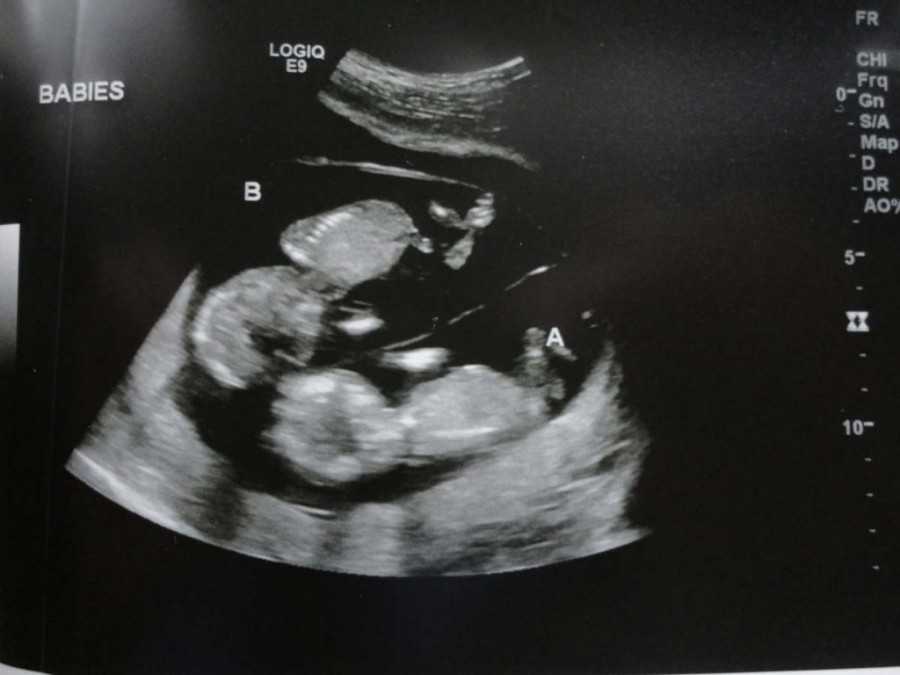

УЗИ на 9-ой неделе беременности

Ваш малыш уже официально именуется плодом, а не эмбрионом, с чем вас и поздравляем!

На УЗИ плода на 9 неделе определяется толщина плаценты и общее состояние пуповины. При помощи допплера, будущая мама может отметить частоту сердечных сокращений малыша. Хотя многие внутренние органы уже достаточно развиты, это не всегда можно увидеть на УЗИ на 9 неделе.

Внутренние органы крохи еще могут выступать в виде пупочной грыжи, но нет повода для беспокойства, ведь это совершенно нормальное явление.

На УЗИ на данном сроке обязательным является общая оценка состояния яичников.

УЗИ на сроке 9 недель